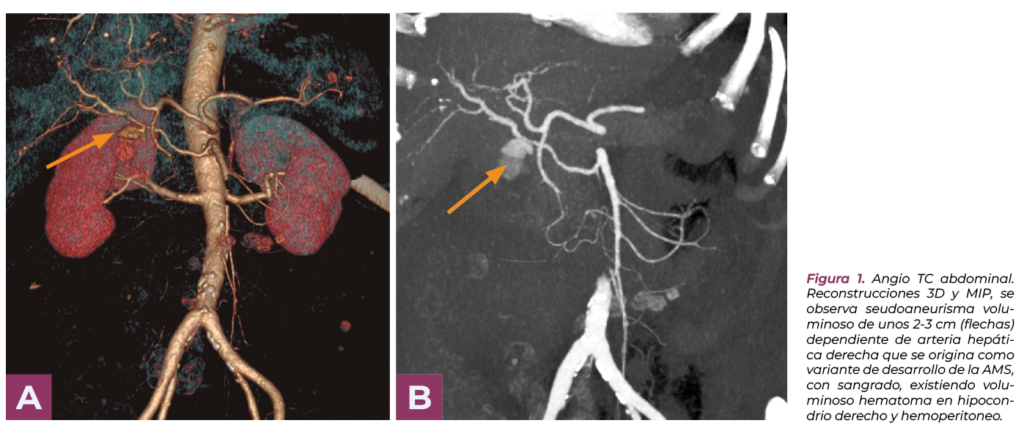

Ante la sospecha de sangrado se realiza angio TC (Fig.1).

En el angio TC se observa un pseudoaneurisma (PAH) de la arteria hepática derecha, voluminoso hematoma en hipocondrio derecho y hemoperitoneo.